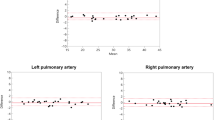

In total, image quality was assessed by each reader for 330 vessels on REACT CMRA and contrast-enhanced steady-state CMRA, respectively (overall ratings, n = 660). 30 vessels (8%) were not assessable on both CMRA methods due to pronounced susceptibility artifacts or congenital or postoperative absence of vessel structures. The overall image quality score was slightly higher for REACT CMRA compared to steady-state CMRA (3.9 ± 1.0 vs. 3.8 ± 0.9, P = 0.018) (Fig. 3A). REACT CMRA achieved a higher image quality score compared to contrast-enhanced CMRA for the ascending aorta, the inferior vena cava, and the origin of the right and left coronary artery (Table 3). A clinical example with a variant origin of a severely hypoplastic native aorta with trifurcation of the coronary arteries is shown in Fig. 4. Image quality of pulmonary arteries was comparable between REACT and steady-state CMRA (Table 3). Image quality of REACT CMRA was slightly lower for the main pulmonary artery (Table 3), which was mainly contributed to flow artifacts due to severe pulmonary insufficiency in single patients. In patients with Glenn shunt (15/36, 42%), the cavopulmonary circulation had a lower blood signal intensity compared with the systemic circulation (Fig. 5A). The image quality of pulmonary veins was intermediate with significant better ratings for contrast-enhanced CMRA (Table 3). An example of a flow artifact is presented in Fig. 5B.

Vessel diameter measurement

Measurements of vessel diameter were performed for 285 landmarks by each reader (overall measurements, n = 570). 39 landmarks (12%) could not be assessed on both CMRA due to severe artifacts or aberrant cardiovascular anatomy. Vessel diameter measurements strongly correlated between both CMRA techniques and showed close intermethod agreement (Pearson r = 0.99; bias = 0.04 ± 0.61 mm, 95% limits of agreement: − 1.17 to 1.24 mm; Fig. 3B, C). Detailed results for vessel diameter measurements are given in Table 4. High ICCs indicated good interobserver reproducibility for the assessment of image quality (REACT: 0.87, contrast-enhanced CMRA: 0.79) and vessel diameter (REACT: 0.99, contrast-enhanced CMRA: 0.99) (Table 5).

REACT-CMRA provided accurate and reliable measurements of vessel diameter comparable to contrast-enhanced CMRA. Although there was a small difference between both methods in the vessel diameter of the inferior pulmonary veins (probably related to impaired image quality due to flow artifacts on REACT CMRA), the difference was still within an acceptable range. The overall image quality score of REACT CMRA was comparable to contrast-enhanced CMRA. Major benefits in image quality were achieved at the ascending aorta including the proximal coronary arteries and at the inferior vena cava.

The slightly impaired image quality for the pulmonary arteries and the intermediate image quality for the pulmonary veins were mainly contributed to artifacts caused by high and turbulent pulmonary flow (especially in patients with severe pulmonary insufficiency or high and turbulent vein flow during diastole). However, clinically relevant abnormalities such as dilatation or stenosis of the pulmonary arteries were adequately assessed compared to contrast-enhanced CMRA. Turbulent flow effects occurred particularly in highly pulsatile circulations like in patients with repaired tetralogy of Fallot. It is known from previous whole heart imaging studies that these effects can be reduced or even compensated by data acquisition in different cardiac phases [27]. Our results indicate that the unique and complex cardiovascular hemodynamics in young children with CHD are not generally comparable with an adolescent or adult cohort [16, 31, 32] and might require dedicated technical adjustments for non-contrast imaging due to pronounced flow-related effects.